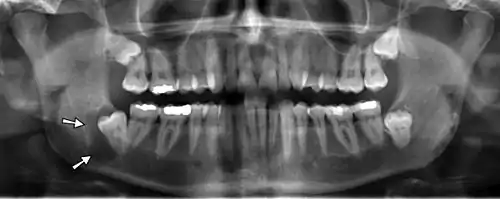

Panoramic radiograph

![]() A dental panoramic radiograph, showing the maxilla and mandible, all the teeth including the "wisdom teeth," the frontal and maxillary sinuses, the nasal cavity and the temporomandibular joint and other near by head and neck anatomy. | |

A panoramic radiograph is a panoramic scanning dental X-ray of the upper and lower jaw. It shows a two-dimensional view of a half-circle from ear to ear. Panoramic radiography is a form of focal plane tomography; thus, images of multiple planes are taken to make up the composite panoramic image, where the maxilla and mandible are in the focal trough and the structures that are superficial and deep to the trough are blurred.